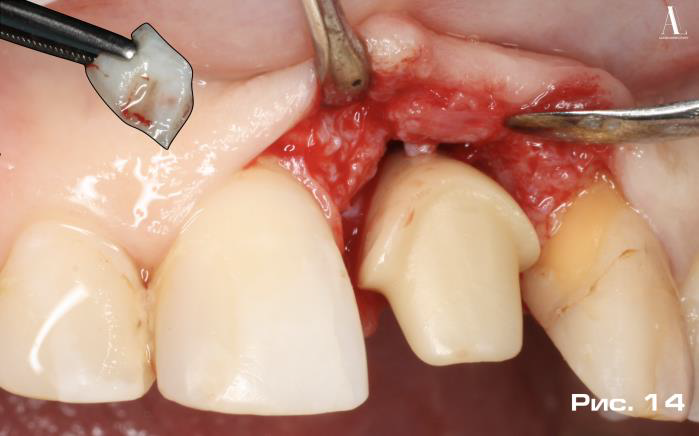

Дополнительное пространство, образованное между абатментом и вестибулярным мукопериостальным лоскутом, ис пользовалось для мягкотканной аугментации с применением свободного соединительнотканного аутотрансплантата, полученного из небной области по методике «Single-incision technique» предложенной Hurzeler M, Weng D в 1999 году (Рис. 14, 15).